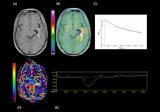

放射性标记抗体的功能化以增强高对比度脑成像的外周清除率

早在2 年前,正电子发射断层扫描 (PET) 药物 [11C]Pittsburg compound B ([11C]PiB),因其与活脑种淀粉样蛋白-β (Aβ) 斑块的结合与可视化,为阿尔茨海默病 (AD)的研究和诊断提供了新的研究方向。然而,进一步的研究表明,在疾病进展过程中,放射性示踪剂的脑滞留保持静止,并且特定APP突变携带者以及Aβ斑块主要弥漫的AD患者的Aβ病理学无法用该方法观察。 2023-02-16 PET/CT放射性示踪剂